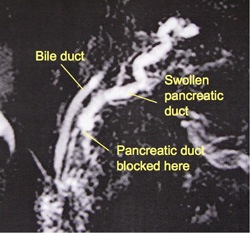

This MRCP picture shows chronic pancreatitis causing a narrowing of the pancreatic duct, with a swollen tortuous duct visible upstreamThe appearance of the pancreas is usually assessed on the basis of a CT scan. The appearance of the pancreatic ducts is assessed by doing an ERCP (an endoscopic procedure) or an MR scan called MRCP.

This MRCP picture shows chronic pancreatitis causing a narrowing of the pancreatic duct, with a swollen tortuous duct visible upstream